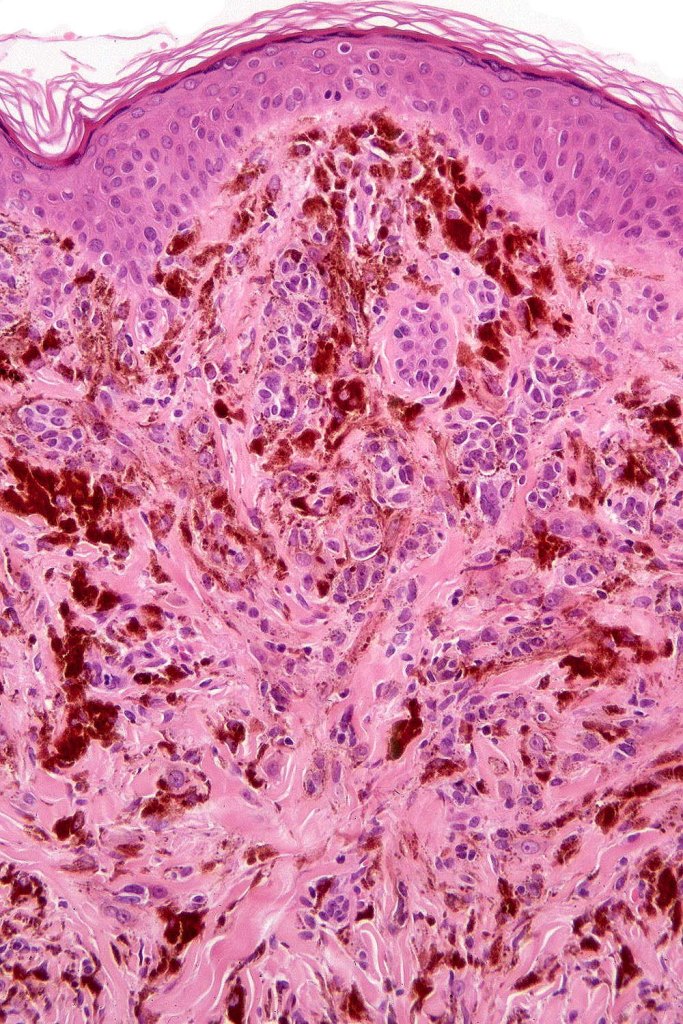

Combined congenital & blue nevus (same case as the clinical photographs coursty of Dr. Antonina Kalmykova